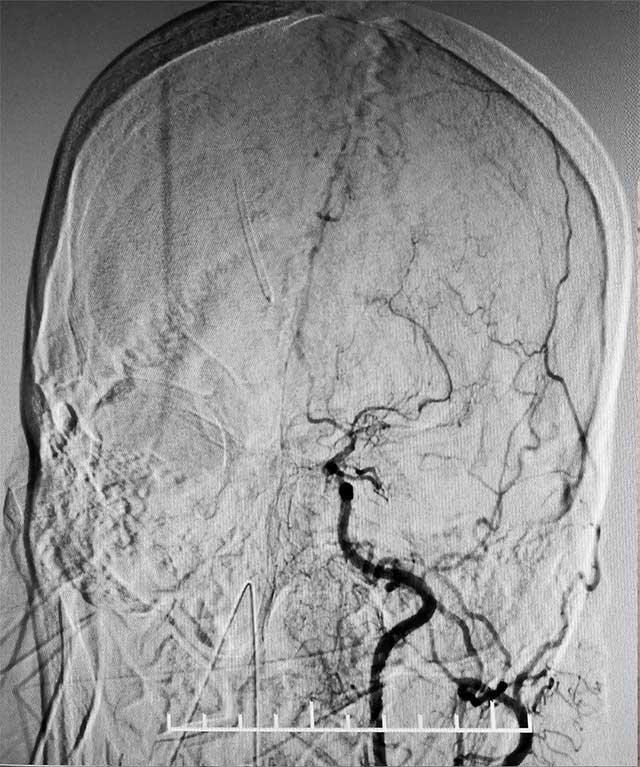

▲ 術(shù)前造影顯示,患者雙側(cè)頸內(nèi)動(dòng)脈末端閉塞,顱內(nèi)煙霧狀血管形成

經(jīng)腦血管CTA和DSA檢查,結(jié)果顯示,患者雙側(cè)頸內(nèi)動(dòng)脈末端閉塞,左側(cè)大腦中動(dòng)脈閉塞,顱內(nèi)煙霧狀血管形成,左側(cè)顳頂枕葉灌注不足明顯,顱底出現(xiàn)細(xì)如煙霧的代償血管網(wǎng)絡(luò),腦部供血嚴(yán)重不足。結(jié)合病史,患者部被確診為煙霧病,由于代償血管壁長期受到異常血流沖擊,形成動(dòng)脈瘤導(dǎo)致腦出血。張琪博士決定為其實(shí)施復(fù)合手術(shù)室下顱內(nèi)外血管搭橋聯(lián)合硬腦膜翻手術(shù)。由于患者腦血流非常薄弱,任何風(fēng)吹草動(dòng),都有可能出現(xiàn)腦梗、腦出血。另外,在手術(shù)過程中,在全身麻醉狀態(tài)下,可能出現(xiàn)血壓降低,造成腦梗。所有這些無疑增加了手術(shù)難度和風(fēng)險(xiǎn)。